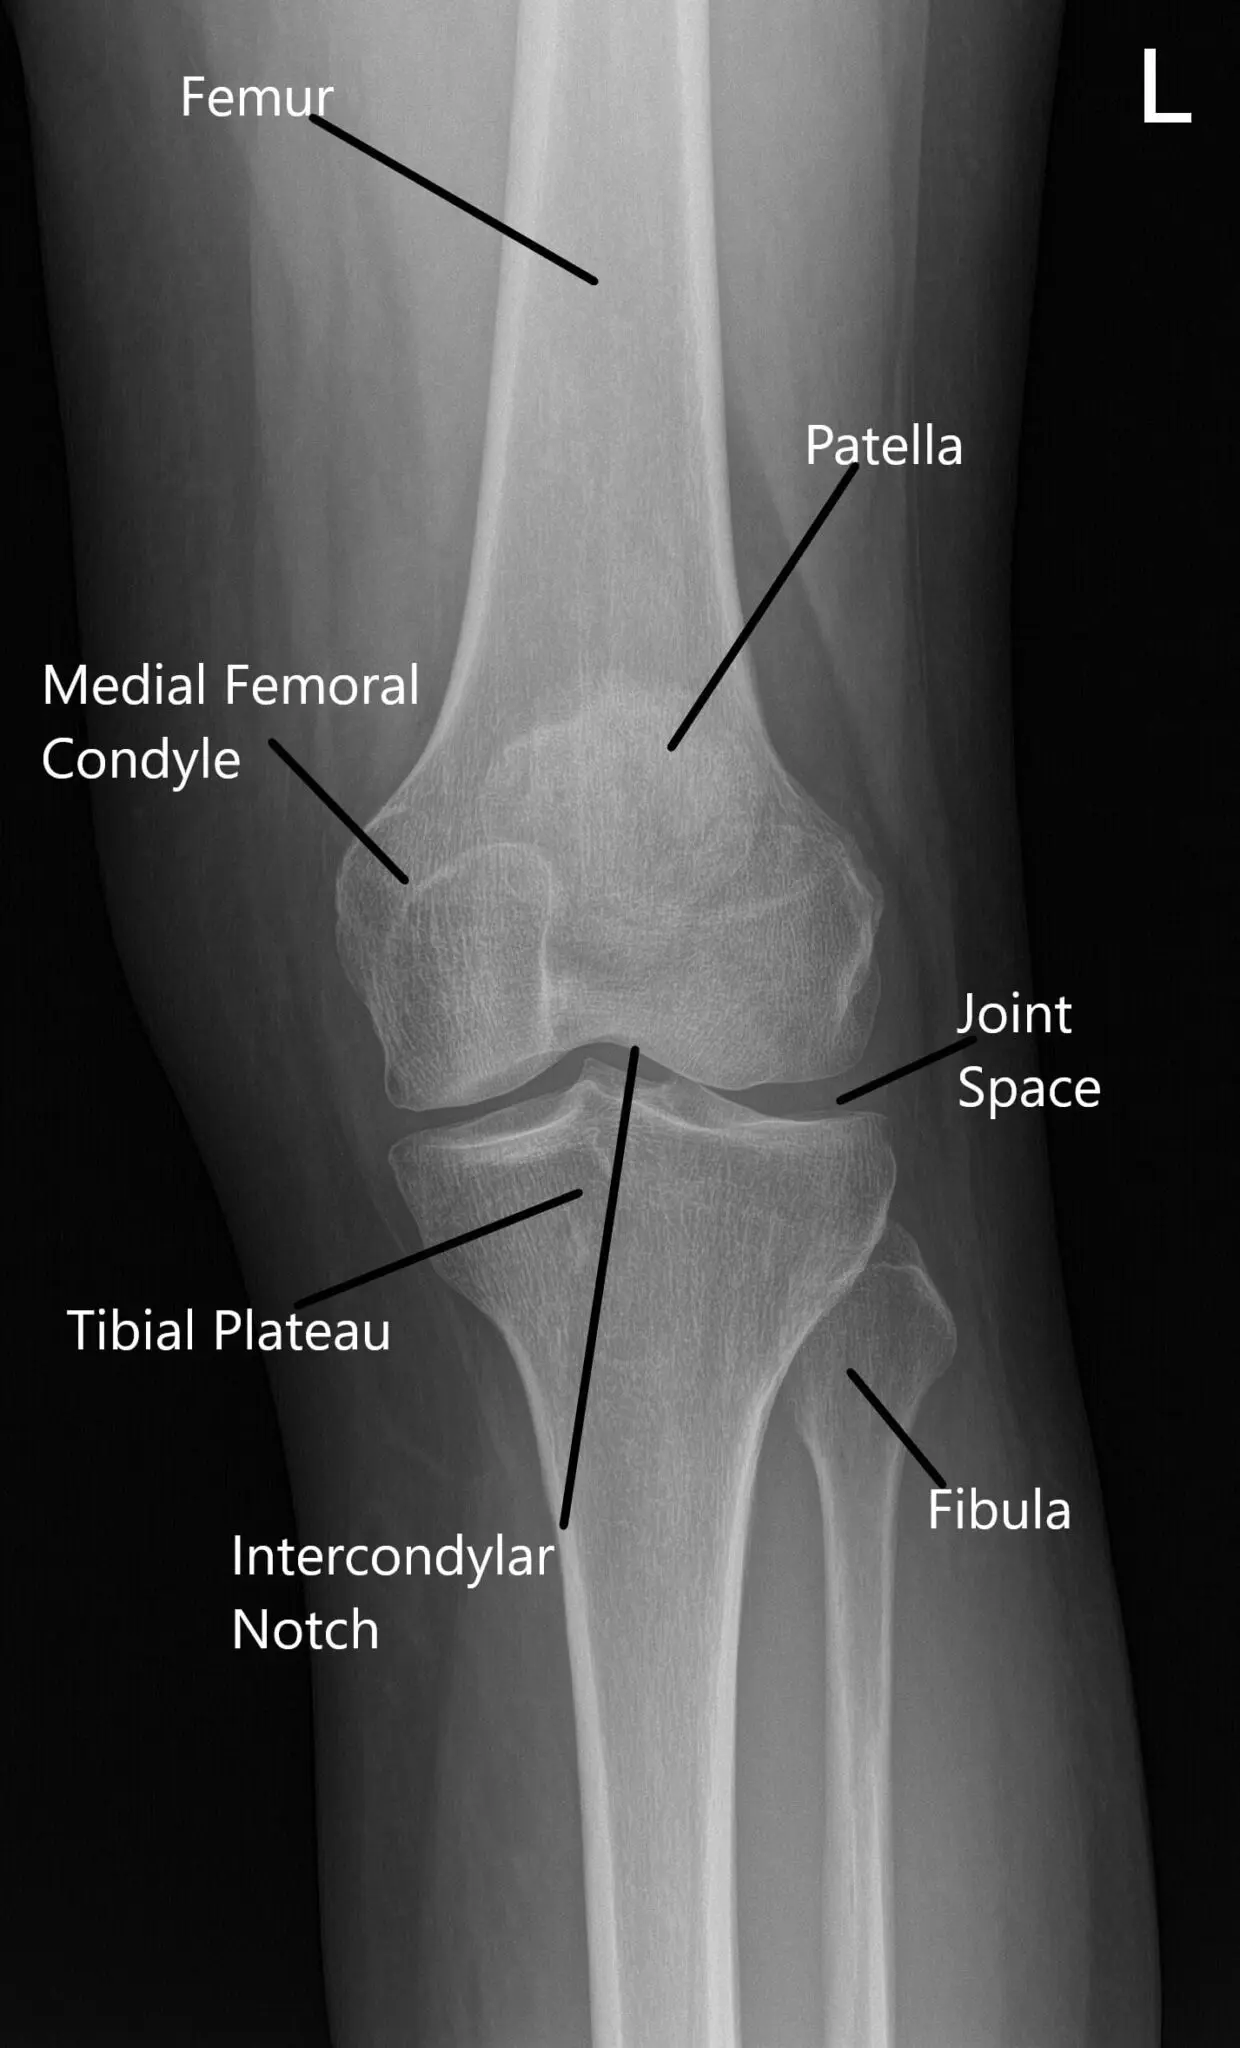

X-ray of the left knee in AP and skyline view of the patella.

The ACL was intact in the intercondylar notch. The cartilage of medial and lateral femoral condyle was intact. There were grade 1 to 2 changes in the trochlea and grade 3 to grade 4 changes in the medial inferior patellar facet.  The inner margin of the medial and lateral meniscus was balanced through a stable margin.